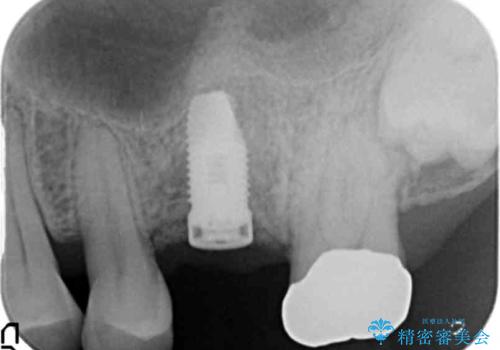

精査したところ上顎骨の厚みが薄かったため、ソケットリフト(上顎洞底挙上術)を併用してインプラント治療を行いました。

インプラントの種類:スプライン ツイスト (保証期間:5年)

クラウンの種類:ベレッツァクラウン (オールセラミック)

固定様式:セメント固定